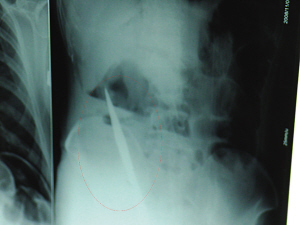

X光片上,尖刀清晰可見。

從男子體內(nèi)取出的尖刀足足有19厘米長(zhǎng)。

銅山一58歲男子因服毒被送到醫(yī)院搶救,可醫(yī)生采取搶救措施后卻發(fā)現(xiàn)效果不佳。后來(lái)經(jīng)細(xì)致檢查,醫(yī)生有了個(gè)驚人的發(fā)現(xiàn),該男子的體內(nèi)竟然有一把尖刀,醫(yī)生通過手術(shù)將位于其腹部右側(cè)橫結(jié)腸下緣的尖刀取了出來(lái)。這把尖刀足足有19厘米長(zhǎng)!據(jù)醫(yī)生推測(cè),這把刀應(yīng)該是從肛門推進(jìn)體內(nèi)的,不知男子為何想以如此殘酷的方式結(jié)束自己生命。由于搶救及時(shí),該男子已暫時(shí)脫離危險(xiǎn)。

6日上午,記者在徐州礦務(wù)集團(tuán)總醫(yī)院重癥監(jiān)護(hù)室見到了這名男子,目前他雖然已經(jīng)恢復(fù)了意識(shí),但還不能開口說話,需要呼吸機(jī)輔助呼吸。據(jù)醫(yī)生介紹,4日中午12時(shí)左右,這名男子因服毒輕生被緊急送到醫(yī)院進(jìn)行搶救,之前,這名男子已經(jīng)在當(dāng)?shù)剜l(xiāng)鎮(zhèn)醫(yī)院進(jìn)行了近20小時(shí)的治療,但效果不佳!安∪吮晦D(zhuǎn)院到礦總院時(shí)已神志不清,血壓極低,處于休克狀態(tài)!本茸o(hù)人員給男子洗胃、初步處理以后,發(fā)現(xiàn)男子呼吸急促,于是趕緊給他拍片檢查。結(jié)果讓所有的醫(yī)生大吃一驚,竟有一把尖狀異物橫在該男子腹腔內(nèi)!當(dāng)天下午5時(shí)30分,輕生男子被推上了手術(shù)臺(tái)。經(jīng)過40多分鐘的手術(shù),該男子腹腔被打開,手術(shù)醫(yī)生發(fā)現(xiàn),男子體內(nèi)的金屬狀異物竟然是一把長(zhǎng)19厘米的尖刀!